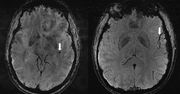

migrena